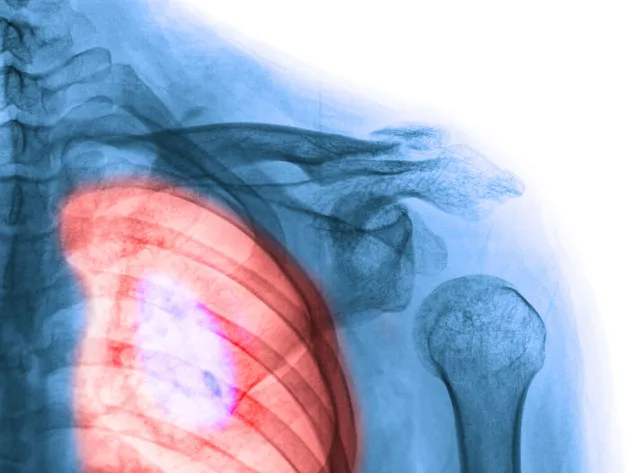

Ministerstwo Zdrowia wraz z Agencją Oceny Technologii Medycznych i Taryfikacji prowadzi działania mające na celu wypracowanie kompleksowego leczenia raka płuc, piersi, jelita grubego, prostaty i narządów kobiecych – poinformowała podczas posiedzenia senackiej komisji zdrowia wiceminister zdrowia Katarzyna Głowala. W Polsce jest bardzo niska pięcioletnia przeżywalność osób chorych na raka. Pięć lat przeżywa zaledwie 10-15 procent pacjentów.

Rak płuc jest pierwszą przyczyna zgonów pacjentów onkologicznych. Według informacji wiceminister Katarzyny Głowali, co roku z tego powodu umiera 16 tysięcy mężczyzn i 7,5 tysięcy kobiet. I właśnie w tej grupie chorych obserwuje się wzrost umieralności. W ocenie wiceszefowej resortu zdrowia powodem jest rosnąca liczba kobiet palących papierosy.

Prof. Chorostowska-Wynimko poinformowała, że w Polsce jest bardzo niska pięcioletnia przeżywalność osób chorych na raka. Pięć lat przeżywa 10-15 procent pacjentów. Profesor podkreśliła, że jedynie leczenie chirurgiczne daje dużą szansę na całkowite wyleczenie. Do tego rodzaju terapii kwalifikuje się jednak zaledwie 20 procent chorych. Jednym z głównych powodów jest późne diagnozowanie choroby nowotworowej płuc. – – powiedziała profesor doktor habilitowany nauk medycznych Halina Batura-Gabryel, krajowy konsultant w dziedzinie chorób płuc. To od nich w dużej mierze zależy prawidłowa diagnoza, a co za tym idzie – szybkie wdrożenie terapii.